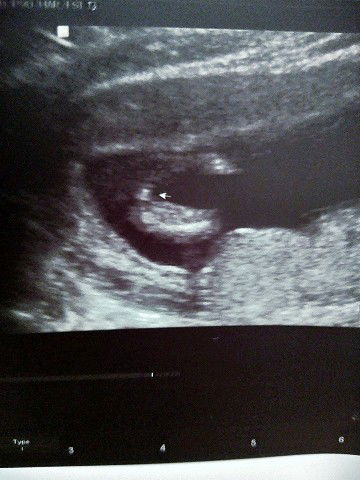

Nagpaultrasound po ako at 14 weeks. Girl po or Boy ?

Looks like a girl po , in some countries as early as 14 weeks nakikita na gender lalo na kung 3D/4D , ulitin nalang 20 weeks up

only an ob sonogram can tell at an earliest of 20 weeks po 😊. at 14 weeks hindi p develop ang reproductive organ ni baby

Usually po 20 weeks above pa nacconfirm if boy/girl kapag formed na ang genitals.